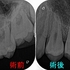

今週1年予後で来院しててもらいました。

レントゲン

2025 EEdental KOE (3).jpg

綺麗に骨が出来上がってくれています!

また1本前の根尖病変に見えた歯の所見も落ち着いているように見えます。